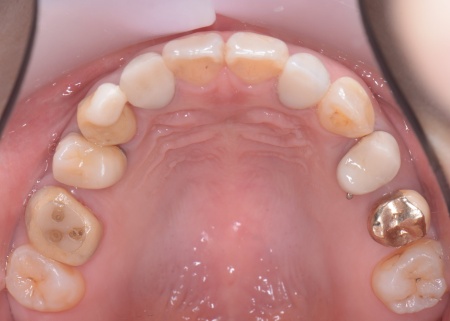

| カウンセリング | 拝見したところ、左下と右上の歯はともに大きな虫歯があり、歯だけでなく被せ物を支える土台の部分にも影響が及んでいました。

さらに、ほかの歯に入っている詰め物や被せ物の周囲にも、過去に治療した部分に再び虫歯ができる二次カリエスが複数見つかりました。 また、噛み合わせを確認したところ、奥歯で噛み合わせた際に上下の前歯が当たらず隙間ができる開咬(かいこう)が認められました。 実際に患者様の場合も、特定の歯に長期間強い力がかかり続けたことで歯や修復物の破損、さらには口腔内全体のトラブルにつながった可能性が高いと考えられました。 修復治療が必要でしたがこの噛み合わせの問題を改善しないまま行うと、治療した歯に再び過度な力が加わって被せ物の破損・脱離や虫歯の再発を招くリスクが高まります。 |

まずは矯正治療を優先し、噛み合わせが整ってから虫歯の再発リスクの低いセラミックの被せ物・詰め物などで歯の形態と機能を回復する方針を提案し、同意いただきました。

矯正治療については、専門的な診断と管理が必要と判断したため専門の矯正歯科医院をご紹介し、他院にて実施していただきました。 矯正治療終了後、改めてお口の中を確認したうえで、歯の状態に合わせ虫歯の除去や土台の修復を丁寧に行い、精密な型取りを実施しています。 最後に噛み合わせ全体のバランスを確認しながら新しく作製した被せ物や詰め物を装着し、見た目に問題がないか、噛み合わせが安定しているかを確認し、治療を終了しました。 |